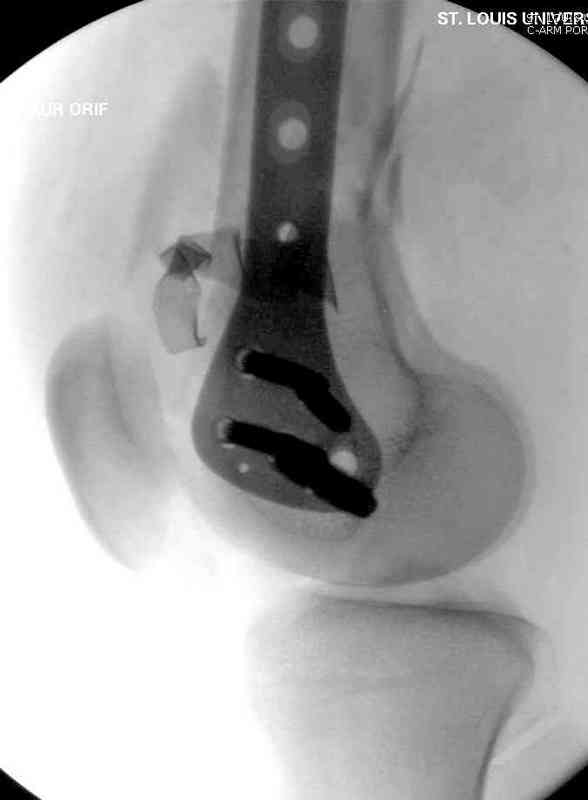

Отправитель: Djoldas Kuldjanov 10 Май 2007, 00:36

Вдогонку..

Вчера утром поступил больной с огнестрельной раной, осмотрен сосудистым специалистом, сделана ангиограмма (снимки) Во время операции при вскрытии обнаружили кровотечение, рану забили салфетками, установили пластину locking DePuy.

Из-за возрастающего давления в компартменте сделана фасциотомия и вызванный сосудистый хирург ушил разрыв вены на уровне перелома. Все раны оставлены открытими, в пятницу закроем.

Djoldas Kuldjanov, MD

Department of Orthopedic Surgery

St. Louis University Medical Center